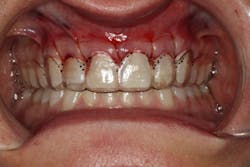

We digitally analyze our esthetics and smile design using the Dawson Diagnostic Wizard (the Dawson Academy). One of our biggest esthetic concerns in this case was caused by a functional issue. As you can see in the photos (figures 1 and 2), the patient has significantly more attritional wear on the right side versus the left. Due to the wear, the right anterior teeth have suffered from more compensatory eruption than the left, which results in uneven gingival architecture and esthetically displeasing length-to-width ratios of the anterior teeth (figures 3 and 4).

When we start to look at our occlusal shots (figures 5 and 6), it is obvious that we have some acidic erosion into dentin as well as significant wear facets from attrition. The pulp chambers of teeth Nos. 8 and 9 are now visible due to the loss of lingual tooth structure.